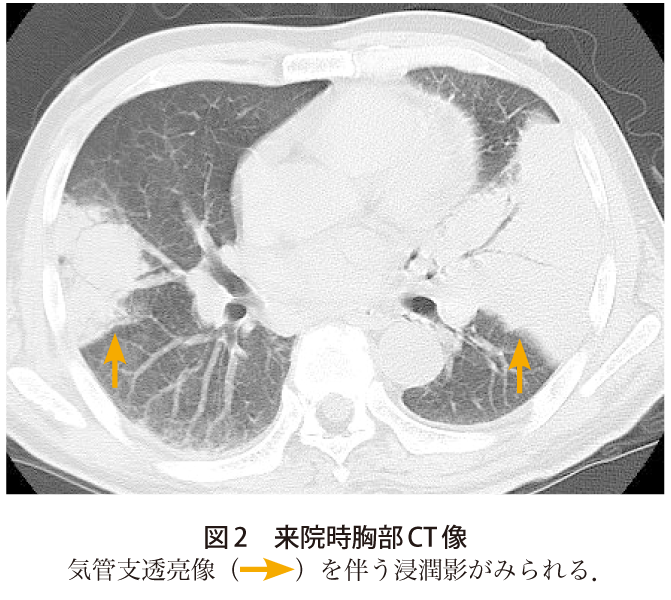

解答 解説 呼吸困難と発熱を主訴とした70歳代男性 実践 画像診断q A 羊土社 レジデントノート 実践 画像診断q A 羊土社 レジデントノート 羊土社

解答 解説 発熱と呼吸困難を主訴とした50歳代男性 実践 画像診断q A 羊土社 レジデントノート 羊土社

解答 解説 高熱 呼吸困難 意識障害で受診した60歳代男性 実践 画像診断q A 羊土社 レジデントノート 実践 画像診断q A 羊土社 レジデントノート 羊土社

解答 解説 高熱を主訴とした60歳代男性 実践 画像診断q A 羊土社 レジデントノート 実践 画像診断q A 羊土社 レジデントノート 羊土社